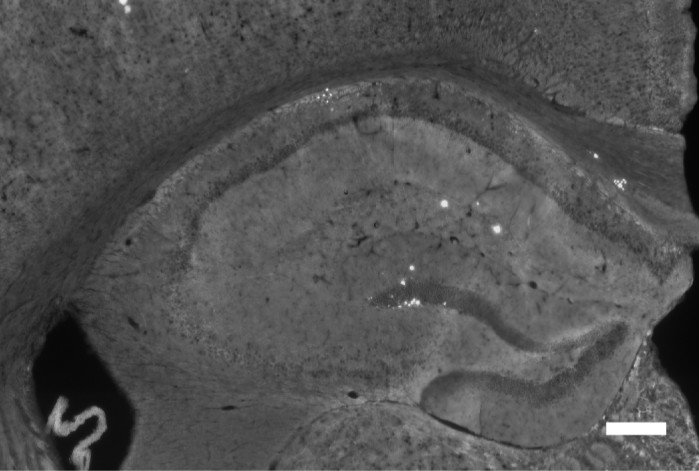

研究團隊透過基因工程,將阿茲海默症小鼠與剔除了CLEC5A基因的小鼠進行育種。跟有記憶缺失的阿茲海默症小鼠相比,那些缺少CLEC5A基因的阿茲海默症小鼠在記憶與學習的行為測試中表現顯著提升,大腦中β類澱粉蛋白的堆積也大幅減少——這些蛋白正是阿茲海默症的關鍵病理指標。

鄭菡若教授表示,微膠細胞(microglia)是腦神經重要的免疫細胞,但阿茲海默症的β類澱粉蛋白異常堆積,也會引發微膠細胞不正常活化而攻擊腦神經。剔除CLEC5A基因後不僅降低微膠細胞的發炎活性,也同時提高對β類澱粉蛋白的清除能力。這意味著CLEC5A基因可能是為治療阿茲海默症的新的治療標的。